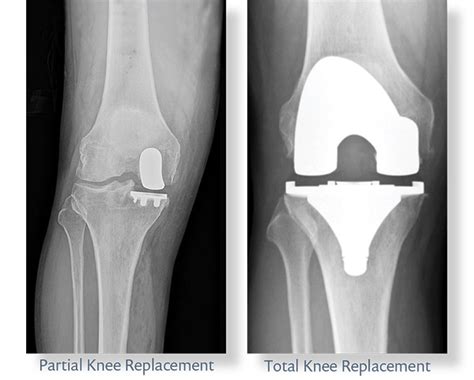

partial knee replacement gone wrong